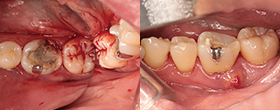

Case1 湾曲根管

• CC「左下奥違和感」主訴に来院

• 左下⑤6⑦Br除去→左下7 2次カリエス認める

• 湾曲大きく穿通せず…ハンドファイルで治療回数5回

EdgeSequel Sapphire™#15/.06テーパーにてグライドパス形成

• 作業長確認

最終拡大#40/.04テーパー